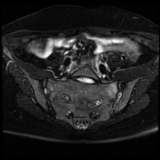

Active axial spondyloarthritis with advanced structural lesions